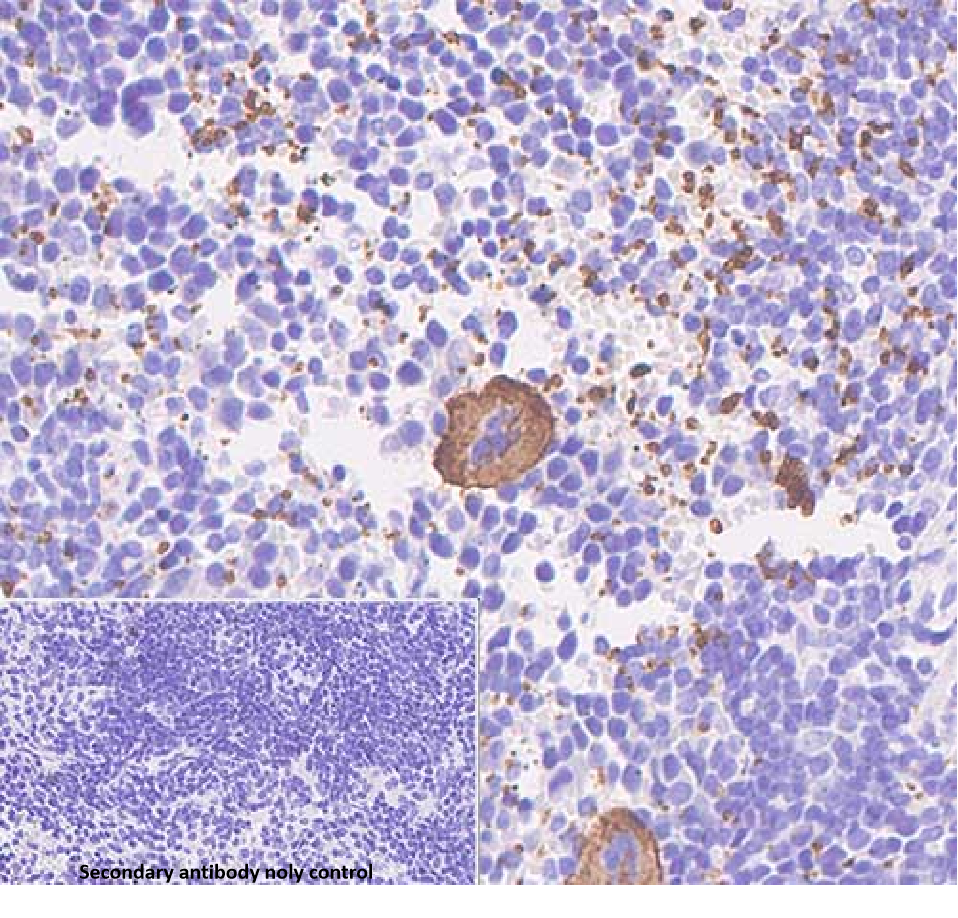

isotype: rabbit monoclonal antibody

Cellular localization: cell membrane

Tissue: paraffin section

CD42b, encoded by the GP1BA gene, is a surface membrane glycoprotein that is expressed on the membranes of megakaryocytes and platelets.CD42b forms part of the CD42b-d complex of surface platelet receptors for vascular endothelial cells (also known as the glycoprotein Ib-IX-V receptor).CD42b can be used to differentiate between acute megakaryoblastic leukemia subtypes.CD42b is negatively expressed in acute myelofibrosis CD42b is negatively expressed in acute myelofibrosis.

CD42b Antibody Reagent binds specifically to CD42b molecular antigen. Immunohistochemistry kits containing CD42b Antibody Reagent are indicated for the precise diagnosis of immune thrombocytopenia (ITP), myelodysplastic syndromes (MDS), and megakaryocytic leukemia.